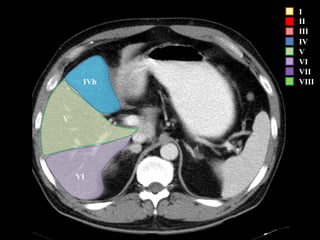

I – Entre cava y porta

II – el más superior de los izquierdos

III – Por debajo del II

IV – por delante de la vesícula

V – por detrás de la vesícula

VI – relación con riñón derecho

VII – el más posterior de los segmentos superiores

VIII – domo hepático

Las claves de la segm. Hepática